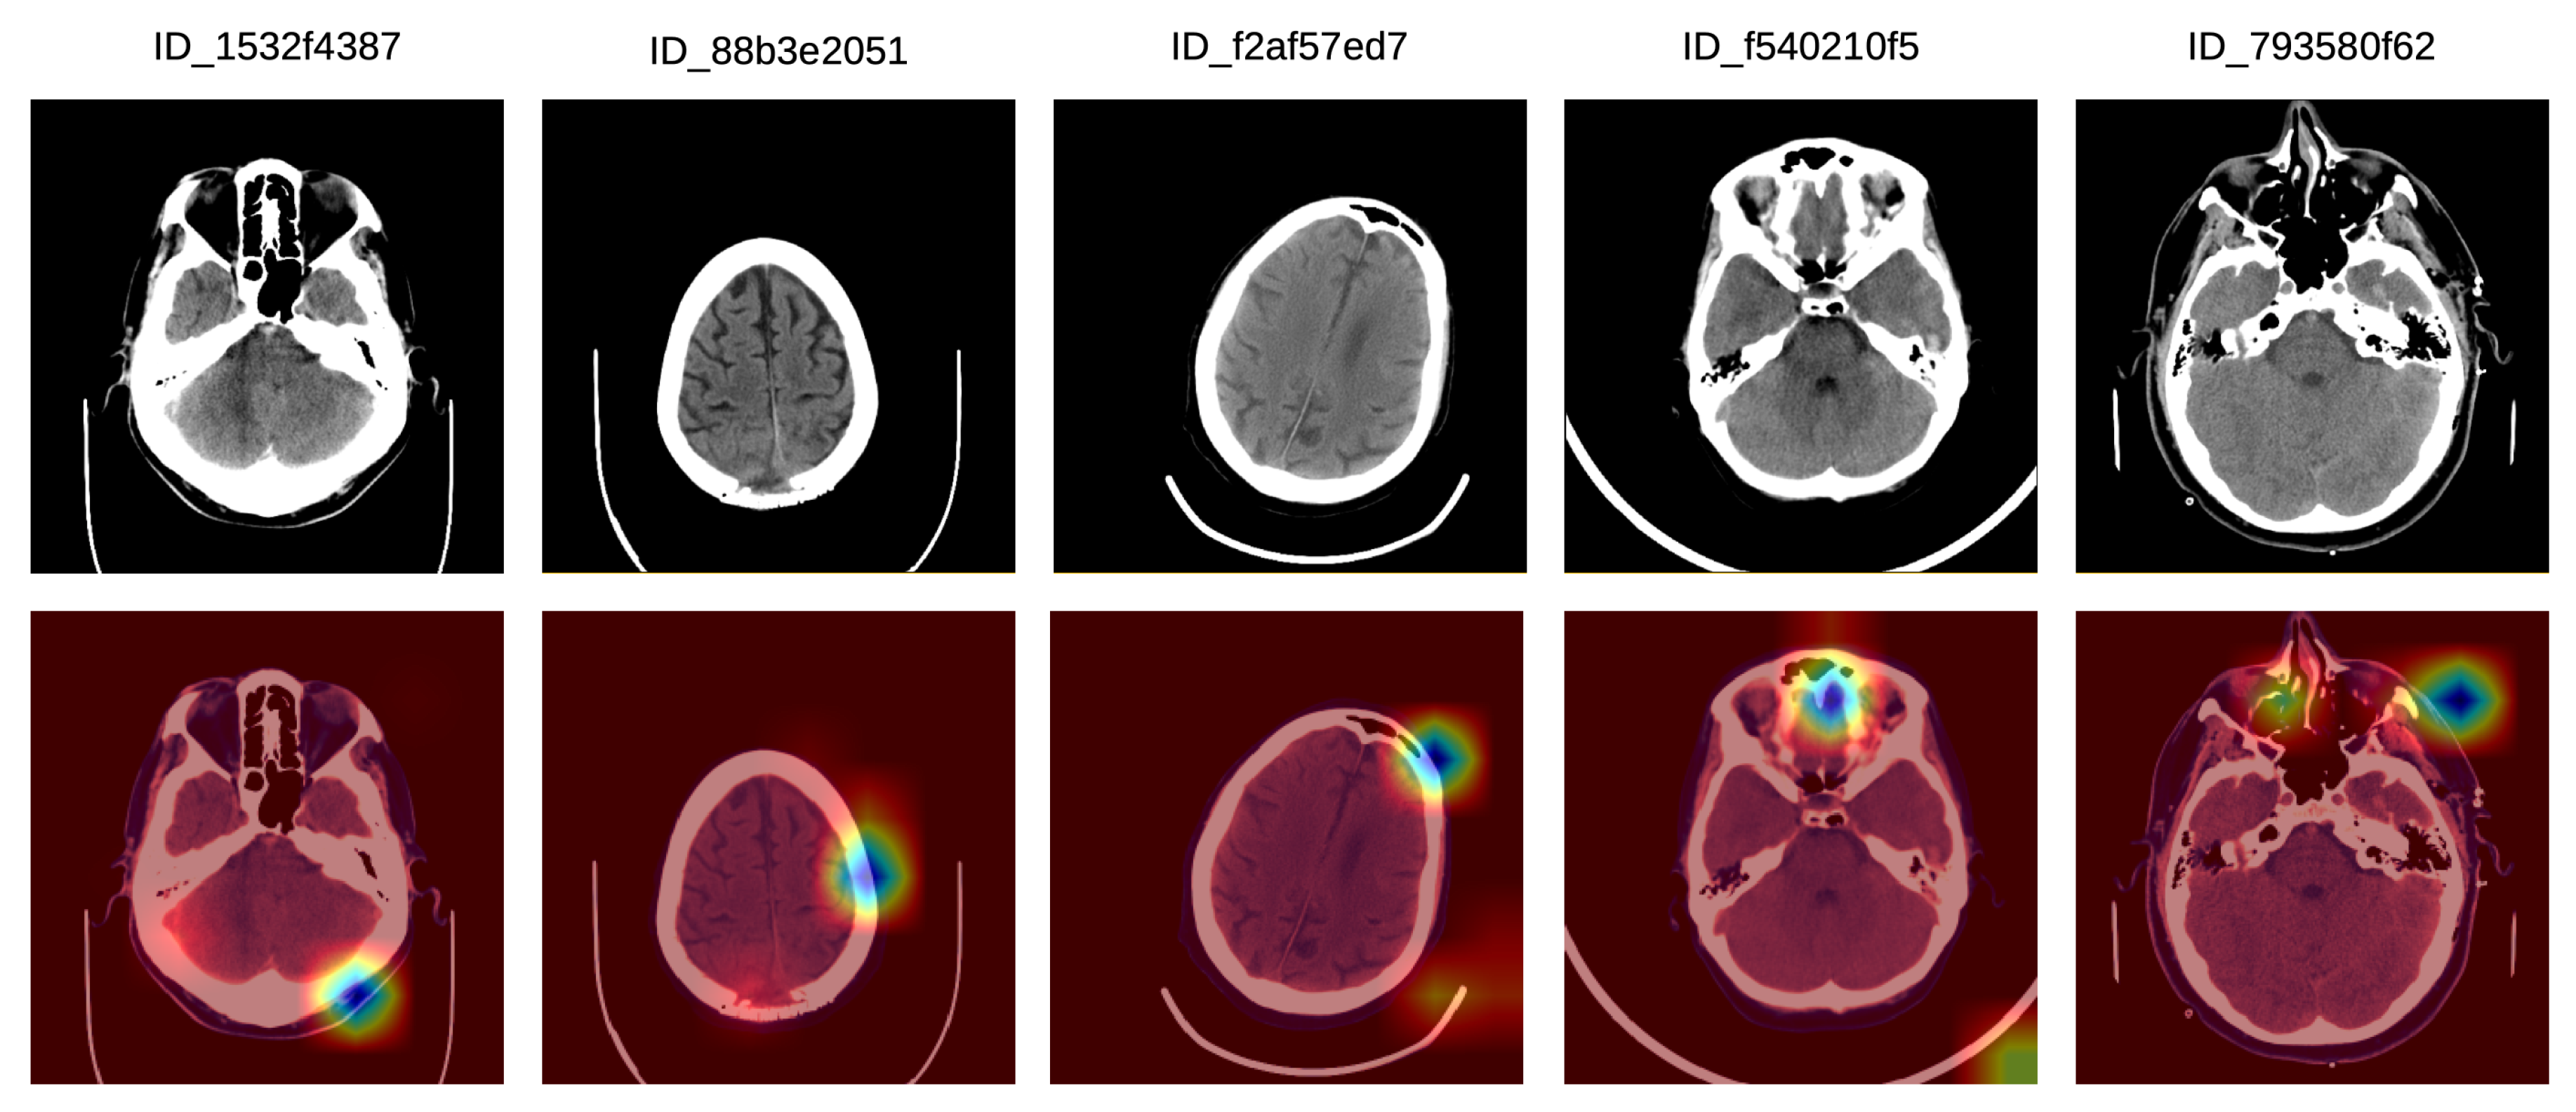

Finally, we illustrate a set of incorrect Grad-CAM visualizations in Figure 7. In the left-most sample, there is a bilateral posterior hemorrhage that is outside the focus area of the system, which seems to have turned its attention on extracranial hemorrhage instead. In the second incorrect example, the system focuses on the left frontal lobe, but the lesion is located in the posterior median parietal lobe. In the third example, there is no intracranial injury, and the system seems to focus mostly on the extracranial area, which is not of interest. In the fourth incorrect visualization, there is a left temporal intraparenchymal lesion outside the focus area of the system, which seems to concentrate on the anterior median region instead. In the fifth example in Figure 7, there is an anterior left temporal lesion which the system does not concentrate on. Instead, the system system focuses on the anterior and the right paramedian regions, and also on the left anterior facial and extracranial mass.

Figure 7.

A selection of Grad-CAM visualizations that are labeled as incorrect by our team of doctors. Best viewed in color.